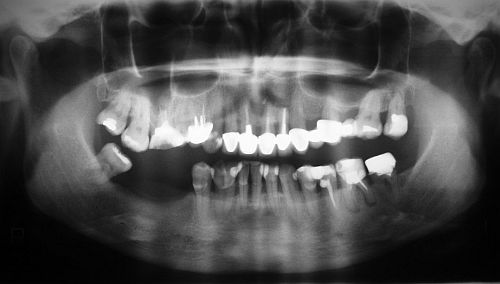

Zdjęcie pantomograficzne /panoramiczne/ – to podstawowe badanie radiologiczne, na podstawie którego możemy ocenić warunki kostne do wprowadzenia implantów dentystycznych.

Podstawowym, najistotniejszym czynnikiem dla powodzenia leczenia implantologicznego jest wystarczająca ilość kości, pozwalająca na wprowadzenie do niej wszczepów o odpowiedniej średnicy i długości. Jej ilość i jakość rzutuje na długoczasowość leczenia i właściwe efekty protetyczne i kosmetyczne. Badania radiologiczne wykonane przed zabiegiem pozwalają nam na dokładną ocenę warunków kostnych i położenia struktur anatomicznych w obrębie szczęk.

Wykonane w odpowiednie skali /np.1:1 lub 1:1,3/ pozwala nam na wykonanie dokładnych pomiarów interesujących nas struktur. Często, przed wykonaniem zdjęcia pantomograficznego do celów implantacyjnych umieszczamy w jamie ustnej tzw. markery, czyli metalowe kulki o średnicy 5 mm, które w obrazie rentgenowskim nie ulegają zniekształceniu. Dzięki nim, stosując później odpowiedni przelicznik związany ze skalą wykonanego zdjęcia mamy możliwość wykonania bardzo precyzyjnych obliczeń.

zdjęcie pantomograficzne

Na podstawie zdjęcia pantomograficznego możemy ocenić:

• stan kości (gęstość, obecność zmian chorobowych, stopień jej zaniku)

• wysokość wyrostka zębodołowego w miejscu planowanej implantacji

• stan zębów

• grubość błony śluzowej

• położenie i rozmiary zatok szczękowych

• przebieg nerwu zębodołowego dolnego

• położenie otworów bródkowych

• odległość do dna jamy nosowej